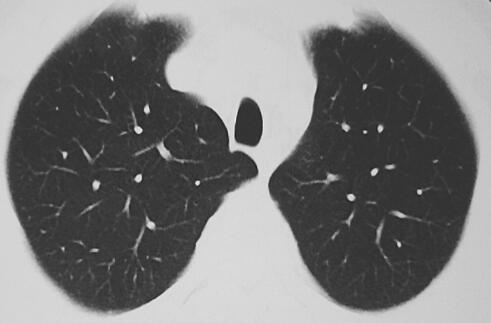

患者,男性,21岁。主诉“发热4个月,喘憋1周”于2010年3月4日来诊。患者自述4个月前一次着凉后出现发热,体温39℃左右。伴咳嗽,干咳为主,少量白痰,发热时伴有头痛、肌肉酸痛,咳嗽时有轻度胸痛。无喷嚏、鼻塞、流涕、咽痛,无呕吐、腹泻,无心悸、腹痛等不适。当地诊所考虑“肺炎”,给予阿莫西林、氨曲南点滴和感冒冲剂、板蓝根口服治疗。间断治疗1个月效果不佳,仍每日发热,偶有畏寒、寒战,体温高峰38~41℃,仍有干咳伴极少量黄白痰,咳嗽时伴有双侧胸部疼痛。遂转至当地市医院呼吸科住院治疗。查血常规:WBC 8.8×109/L,N 73.6%,Hb 130g/L,PLT 117×109/L;肝功能:TBil 39.2μmol/L,DBil 20.0μmol/L,ALT 110U/L,Alb 30g/L;肾功能:Cr 88μmol/L,BUN 6.51mmol/L;心肌酶谱:CK 329U/L,CKMB 73μg/L,LDH 1092U/L;尿便常规正常;心电图提示窦性心动过速。查肺炎衣原体抗体1∶40,冷凝集试验1∶64;肺炎支原体抗体、军团菌抗体、结核分枝杆菌抗体均阴性;查胸部CT提示少许条索影(图1)。

图1 入院时胸部CT